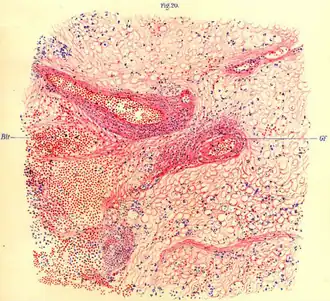

| Мозговая ткань обезьяны, пораженная летаргическим энцефалитом (из von Economo's Die Encephalitis lethargica (1918)) | |

Для эпидемического энцефалита характерно поражение базальных ядер и ствола мозга. Страдают преимущественно клеточные элементы. При микроскопии обнаруживаются выраженные воспалительные изменения: периваскулярная инфильтрация мононуклеарами и плазматическими клетками в виде муфт, значительная пролиферация микроглии, иногда с образованием глиозных узелков. В хронической стадии наиболее выраженные изменения локализуются в чёрном веществе и бледном шаре. В этих образованиях отмечаются необратимые дистрофические изменения ганглиозных клеток. На месте погибших клеток формируются глиозные рубцы[19].